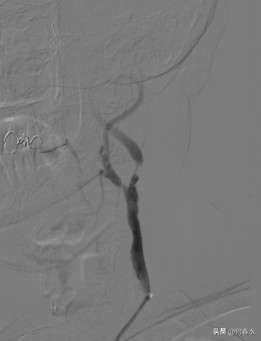

影像资料如下:

图片说明:造影显示,颈内动脉起始段重度狭窄,狭窄率达95%